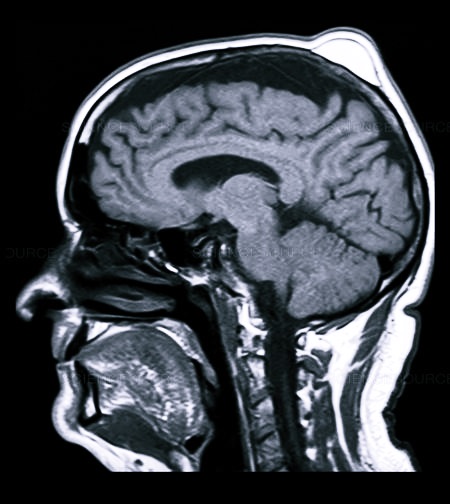

Первичный диагноз выставляется на основании внешнего осмотра, жалоб больного, данных анамнеза. Для его подтверждения иногда требуется проведение ряда инструментальных исследований:

- МРТ или КТ;